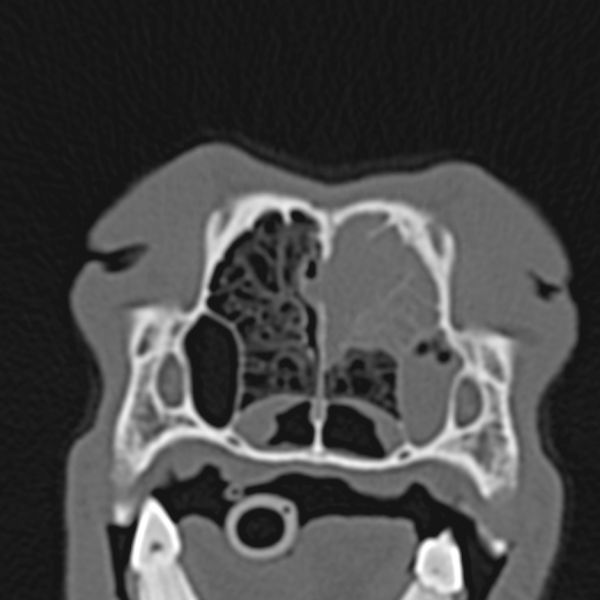

Die Computertomographie ermöglicht die Erstellung detaillierter, dreidimensionaler Bilder des Körperinneren eines Tieres. Im Gegensatz zu herkömmlichen Röntgenaufnahmen, die lediglich zweidimensionale Überlagerungen von Strukturen darstellen, liefert der CT-Scan Schichtaufnahmen, die eine präzise Beurteilung von Knochen, Weichteilen und Organen ermöglichen. Diese Technologie ist besonders wertvoll bei der Diagnose von Tumoren, Verletzungen, Entzündungen und anderen Erkrankungen, die mit herkömmlichen Methoden schwer zu erkennen sind.

Ein kritischer Aspekt der CT-Technologie ist die Strahlenbelastung. Obwohl moderne CT-Geräte die Dosis minimieren, ist sie dennoch vorhanden. Tierärzte sind verpflichtet, die Strahlenbelastung so gering wie möglich zu halten, indem sie nur notwendige Scans durchführen und geeignete Schutzmaßnahmen ergreifen. Ein weiterer entscheidender Faktor ist die Bildauflösung. Eine hohe Auflösung ermöglicht die Darstellung feinster anatomischer Details, was insbesondere bei kleinen Tieren oder bei der Beurteilung subtiler Veränderungen von Bedeutung ist. Die Investition in hochwertige CT-Geräte ist daher ein Qualitätsmerkmal einer fortschrittlichen Tierarztpraxis.